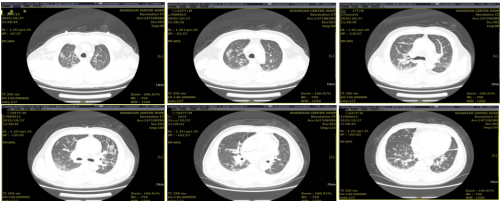

10月27日胸部CT示:双肺间质性改变;双侧胸腔积液并双肺下肺膨胀不全。